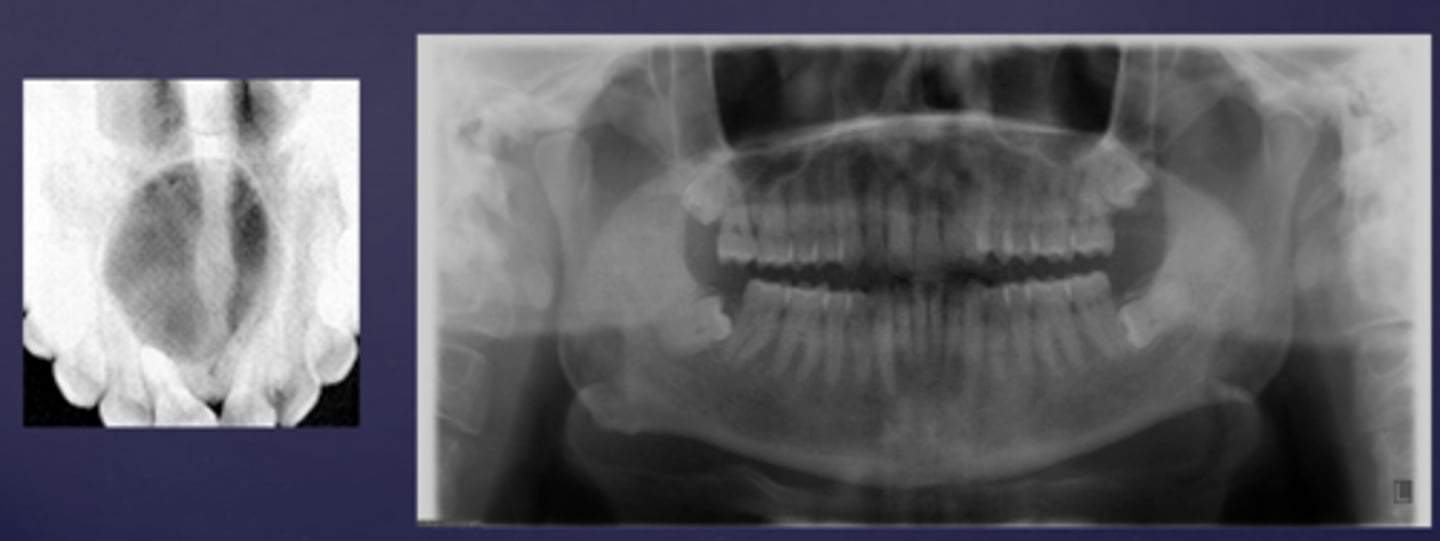

How would you describe these lesions?

- Defined, corticated midline maxillary radiolucency

- Causing tooth displacement in the occlusal image

What category would these lesions be part of?

Benign

What would be a differential diagnosis for these lesions?

Incisive/nasopalatine duct cyst

(Pan and occlusal are not from the same case but they share the diagnosis)